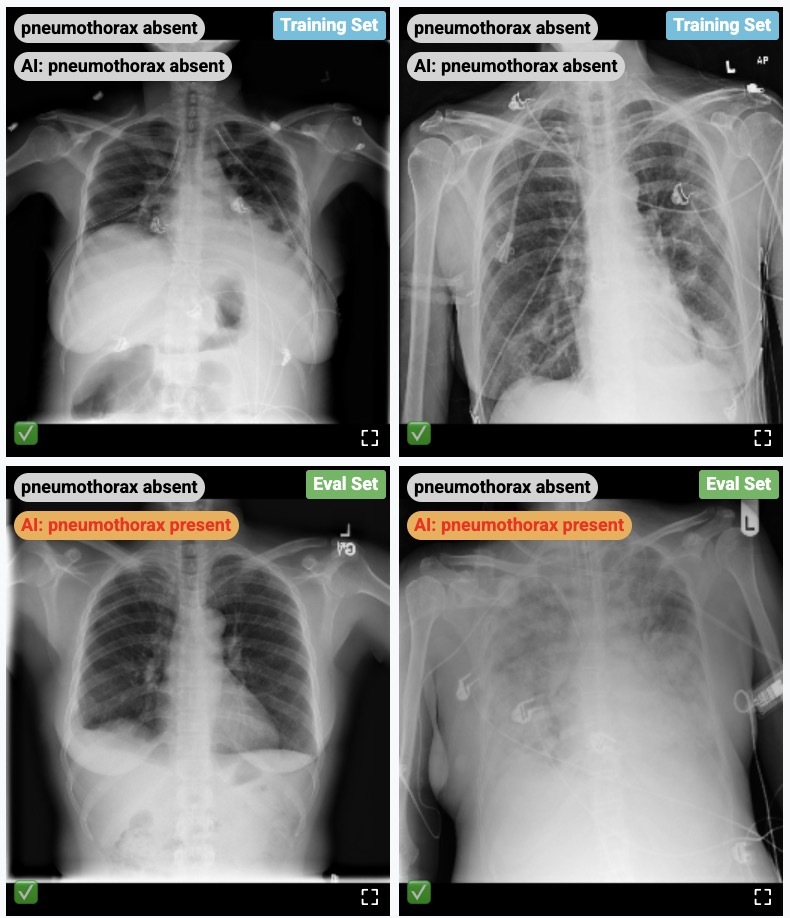

Demo usage of the CXR Foundation model embeddings

A demo showcasing a medical learning experience of CXR image